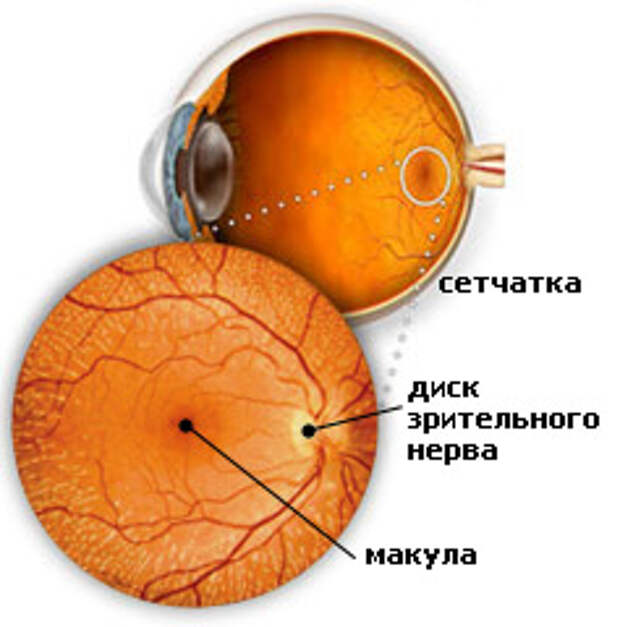

Изображения и анатомия сетчатки глаза